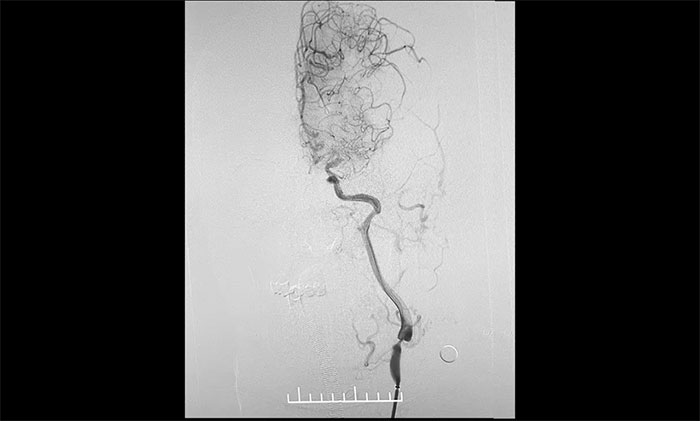

術中,席剛明教授、王貴平博士克服血管迂曲困難,經(jīng)過多次嘗試,多次球囊擴張、“按摩”后,最終順利釋放密網(wǎng)支架至左頸內動脈眼動脈段、左頸內動脈床突段、左頸內動脈海綿竇段。造影及3D造影見,動脈瘤瘤內造影劑明顯滯留,左頸內動脈、左大腦前動脈顯影可,載瘤動脈通暢,獲得了理想的血管重建。復查造影,左頸總動脈造影見左頸總動脈、左頸內動脈、左大腦前動脈顯影可。CT見支架打開貼壁滿意,XperCT未見顱內出血,手術圓滿完成,順利拆除“不定時炸彈”并打通大腦生命線。

▲ 血管極度迂曲,為手術帶來挑戰(zhàn)

▲ 頸動脈重度狹窄解除,打通大腦生命線

▲ 順利拆除“不定時炸彈”